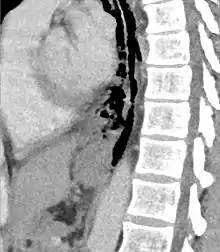

| Axial CT image through the upper chest showing extraluminal air (Pneumomediastinum) surrounding the trachea and esophagus | |